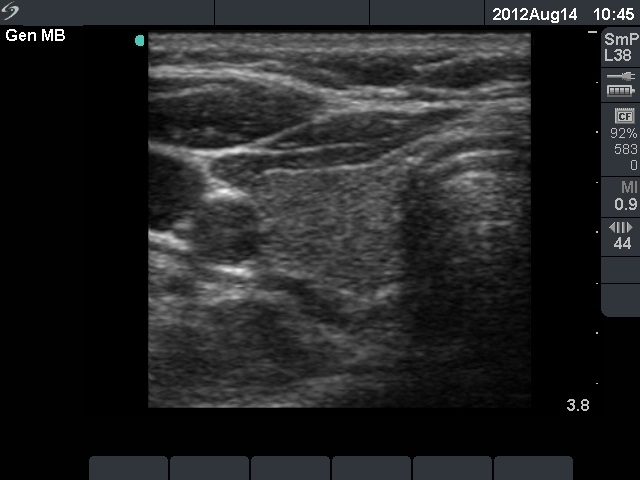

First examination (1st and 2nd rows of images):

Clinical presentation: a 45-year-old woman was referred with typical complaints of subacute thyroiditis: fever, pain in the region of the left thyroid lasting for 4 weeks.

Palpation: the left thyroid was hard and painful, while the right thyroid was moderately firm and not tender.

Functional state: moderate degree of hyperthyroidism with TSH-level 0.001 mIU/L, FT4 35.1 pM/L. ESR 70 mm/H, CRP 21.7 mg/L.

Ultrasonography: there were multiple hypoechogenic areas with blurred borders within echonormal background in the left thyroid. The vascularization was decreased. The right thyroid was intact and had normal vascularization.

Cytological diagnosis: subacute, granulomatous de Quervain's thyroiditis.

Suggestion: steroid therapy. The complaints of the patient suddenly stopped within 24 hours after the steroid intake.